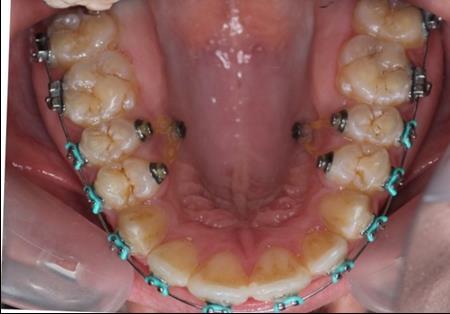

Figure 4.Intraoral photography at the start of the treatment.

After obtaining the informed consent the orthodontic treatment began and 0,22 Roth straight-wire fixed appliances were bonded. After leveling and aligning, during upper arch expansion, we took impressions and made intermediate study models. We noticed that palatal cusps of the upper premolars could not be intruded by classic mechanics. We decided to intrude first and second bicuspids to resolve the open bite. Skeletal anchorage was indicated and two orthodontic mini-implants were inserted on the palatal side between the premolars.